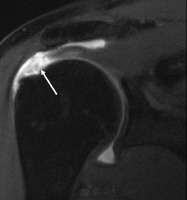

MRI of normal shoulder intratendinous signal

MRI of rotator cuff full-thickness tear

Tears of the rotator cuff tendon are described as partial or full thickness, and full thickness with complete detachment of the tendons from bone.

Shoulder pain is variable and may not be proportional to the size of the tear.